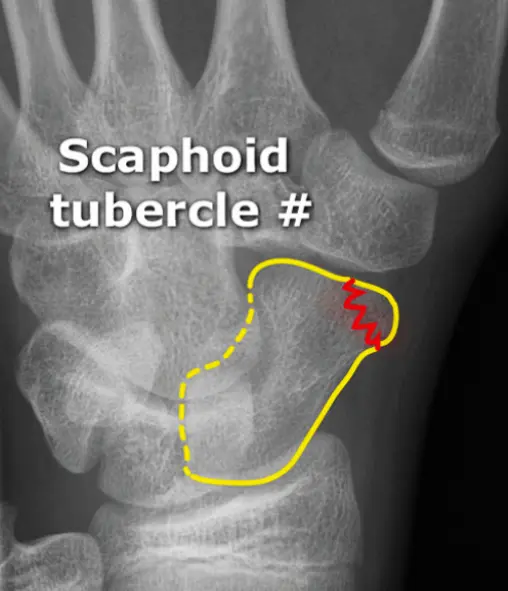

Follow the Cortex

- x-ray of wrist undisplaced fracture of scaphoid

- In Trauma â âFollow the Cortexâ â adjust brightness/contrast to reveal the fracture line.

A 29âyearâold man fell from a ladder and presents with pain in the wrist.

- Site â wrist

- Type â (Specify fracture type)

- Fracture line â (Describe orientation)

- Displacements â (Note any displacement)

- Special issues â (Highlight any neurovascular or softâtissue concerns)